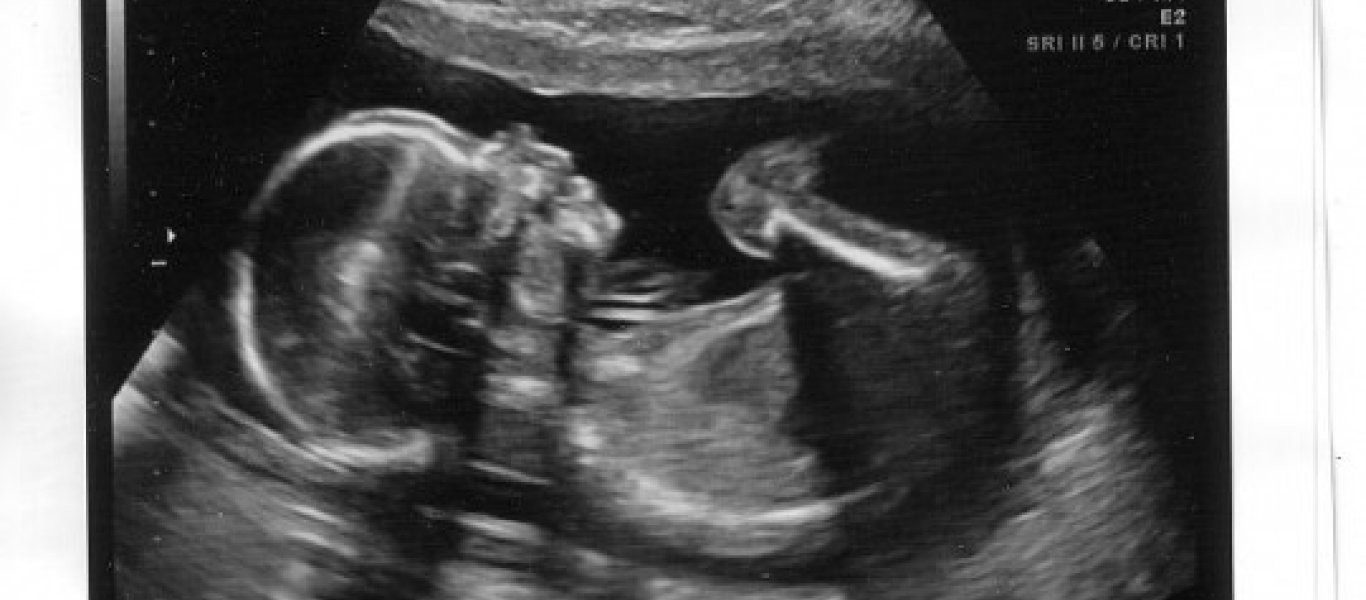

Τί είδαν οι γονείς στο υπερηχογράφημα αυτού του μωρού και δεν το περίμεναν! (φωτό)

Η μικρή Alexis Bartlett γεννήθηκε με πολλά καστανά μαλλάκια! Μάλιστα, μόλις λίγες βδομάδες στην κοιλιά της μαμάς της, και το υπερηχογράφημα έδειχνε τα μακριά της μαλλιά!Για κάποια μωρά πρέπει να περάσ...